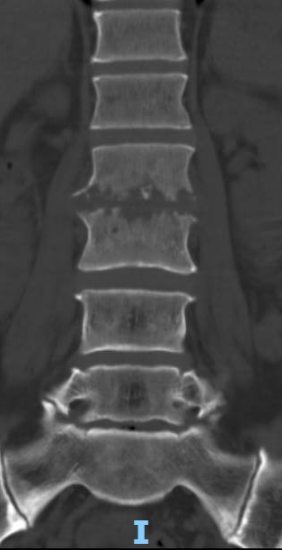

术前腰椎CT

患者出院后感腰部疼痛持续加重,到飞禽走兽攻略站 门诊就诊,以“腰椎感染”收住入院。患者发病后腰椎CT及MRI均提示腰2-3椎间隙变窄,椎板破坏,综合以上资料诊断”腰椎结核”。入院后经口服四联抗结核药物治疗3周,患者自觉腰部疼痛减轻,午后无发热及盗汗后,在全麻下行颈后路病灶清除、椎间植骨、椎弓根钉棒系统内固定术。手术顺利,术后继续抗结核治疗。患者恢复顺利,术后1周下床活动,无特殊不适。术后2周拆线、出院,院外继续口服抗结核药物治疗,定期门诊复查。